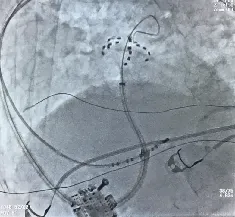

术中造影显示患者下腔静脉极度迂曲,无法经下腔静脉途径送入导管。团队果断改为左腋静脉入路,使用AccuSafe穿刺导丝联合Navigo 8.5Fr可调弯鞘进行房间隔穿刺,并采用本中心首创的Y阀造影剂显影方法确认进入左房。术中借助可调弯鞘灵活适配至上腔静脉入路角度,实现与房间隔稳定贴靠;依托穿刺导丝的滑脱保护及穿刺兼导引的双重安全特性,避免了误穿心包、主动脉及鞘管前冲损伤,在X线引导下精准、安全完成穿间隔操作,充分体现了团队的娴熟技术与应变能力。随后送入Farapulse PFA导管,对双侧肺静脉及上腔静脉进行消融隔离,共放电37次,验证完全阻断,手术获得成功(见图4)。

左1左2为房间隔穿刺过程;右1肺右上肺静脉花瓣状消融;右2:左上肺静脉网篮状消融